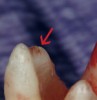

Round burs have three inherent problems. Tip size is the first issue (Figure 10). The tips are simply too big. The second problem is shape. The resultant irregular and parallel-sided cavity walls formed by a round bur work against the clinician when attempting to insert a hand file. When clinicians rummage around the calcified tooth with a round bur, it is common for the bur to become slightly misdirected. Then when inserting a file, it clunks into the bottom of the "well." The clinician has no choice but to continue to tunnel deeper and go back and forth, clunking hand files into the fruitless bottom and then burrowing deeper with round burs. In most cases, the wisp of pulp was higher up, like a trap door on the side wall (Figure 11).

The third problem with round The third problem with round burs is their tendency to gouge during de-roofing. Khademi maintains that it is truly impossible to cut flat walls in three dimensions with a round (round bur) instrument. 16 What happens instead is that the chamber is not unroofed in some areas, which leaves pulpal and necrotic debris, with no specific subsequent step to address the debris. Yet the walls are overextended and gouged in other areas. Further, the internal radius of curvature at many of the pulp chamber line angles is simply too small for all but the smallest of round burs.